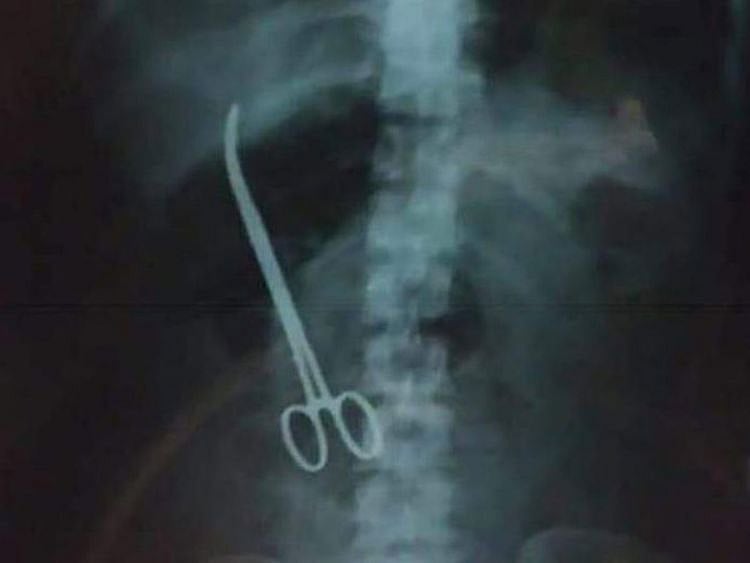

X-ray shows a pair of scissors in a woman's stomach

The incident came to light on Saturday when an X-ray report revealed that a pair of forceps was embedded in the stomach of Maheshwari Chowdary.